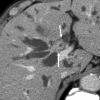

IgG4-related sclerosing cholangitis (IgG4-SC) is a distinct type of cholangitis frequently associated with autoimmune pancreatitis and currently recognized as a biliary manifestation of IgG4-related disease. Although clinical diagnostic criteria of IgG4-SC were established in 2012, differential diagnosis from primary sclerosing cholangitis and cholangiocarcinoma is sometimes difficult. Furthermore, no practical guidelines for IgG4-SC are available. Because the evidence level of most articles retrieved through searching the PubMed, Cochrane Library, and Igaku Chuo Zasshi databases was below C based on the systematic review evaluation system of clinical practice guidelines MINDS 2014, we developed consensus guidelines using the modified Delphi approach. Three committees (a guideline creating committee, an expert panelist committee for rating statements according to the modified Delphi method, and an evaluating committee) were organized. Eighteen clinical questions (CQs) with clinical statements were developed regarding diagnosis (14 CQs) and treatment (4 CQs). Recommendation levels for clinical statements were set using the modified Delphi approach. The guidelines explain methods for accurate diagnosis, and safe and appropriate treatment of IgG4-SC.